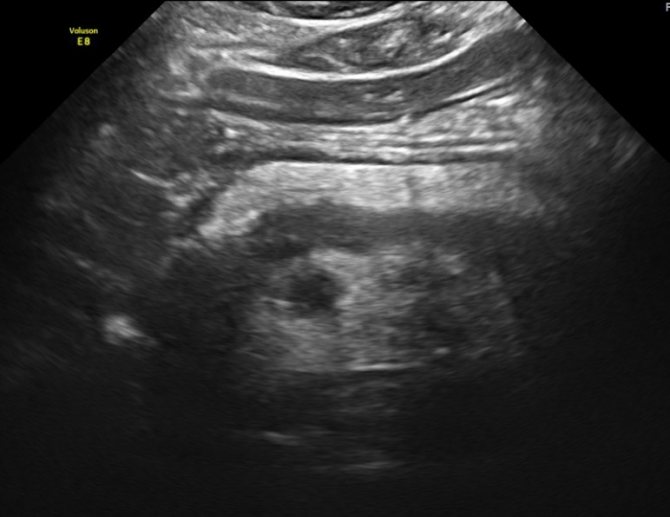

Рак на УЗИ выглядит в виде объёмного образования в структуре органа. Оно может выявиться в зоне головки, тела или хвоста. На УЗИ визуализируется размер, форма и плотность опухоли. При раке головки отмечают её увеличение. Она приобретает округлую форму. Выявляют распространение злокачественного процесса на соседние органы, прорастание опухоли в близлежащие сосуды, появление метастатических очагов в лимфатических узлах.

Опухоль на мониторе аппарата УЗИ просматривается в качестве объемного новообразования, имеющая неправильную форму и неровные края. Наблюдается изменение тканей поджелудочной железы низкой эхогенности. Образование неоднородной структуры. Нередко возникают сложности дифференциации образования от псевдотуморозной формы панкреатита, потому требуется тщательное исследование панкреатического канала. При болезни основной панкреатический проток выглядит расширенным, на своем протяжении его диаметр неравномерный. Когда есть рак, канал расширяется только ниже опухоли.

При проведении УЗИ можно увидеть характерный эхопризнак ракового новообразования — значительное увеличение отдельной части железы или выбухание ее контура. В 50-80% случаев в онкозаболевание вовлекается головка ПЖ. Даже опухоль незначительных размеров является хорошо видимой в головном конце на УЗИ. Это связано со следующими причинами:

Возможно поражение опухолью всей ткани ПЖ — мультицентричный рост. Картина, которая визуализируется на УЗИ, напоминает диффузный отек при остром панкреатите.

При раке ПЖ изменяются контуры органа: они становятся нечеткими, но, в отличие от хронического панкреатита, не имеют неровностей или зазубрин. В месте расположения опухоли визуализируются выпуклости, которые проникают в окружающую клетчатку в виде языков. Все это подробно описывается в заключении УЗИ.

В основном раковое образование ПЖ является гипоэхогенным, в нем не содержится внутренних эхоструктур. Но бывают опухоли с диффузно определяющимися эхосигналами или высокоинтенсивными эхосигналами в центре узла при отсутствии их на периферии опухоли. Граница между измененной опухолью и остальной тканью железы может быть нечеткой, но приблизительно видна всегда за счет разности в эхогенности нормальной и патологической ткани. Несмотря на схожесть структуры ткани образования (особенно если в ней отсутствуют участки структур с повышенной плотностью) с кистой, УЗИ с помощью эффекта дистального усиления дает возможность отдифференцировать злокачественный очаг от жидкостного образования.

При наличии опухоли в головке ПЖ анализируются данные расширенного вирсунгова протока: при раке выявляются ровные и неуплотненные стенки, в отличие от их изменений при хроническом панкреатите. Если диаметр главного выводного протока равен примерно половине толщины самой ПЖ, это является одним из признаков злокачественного процесса.